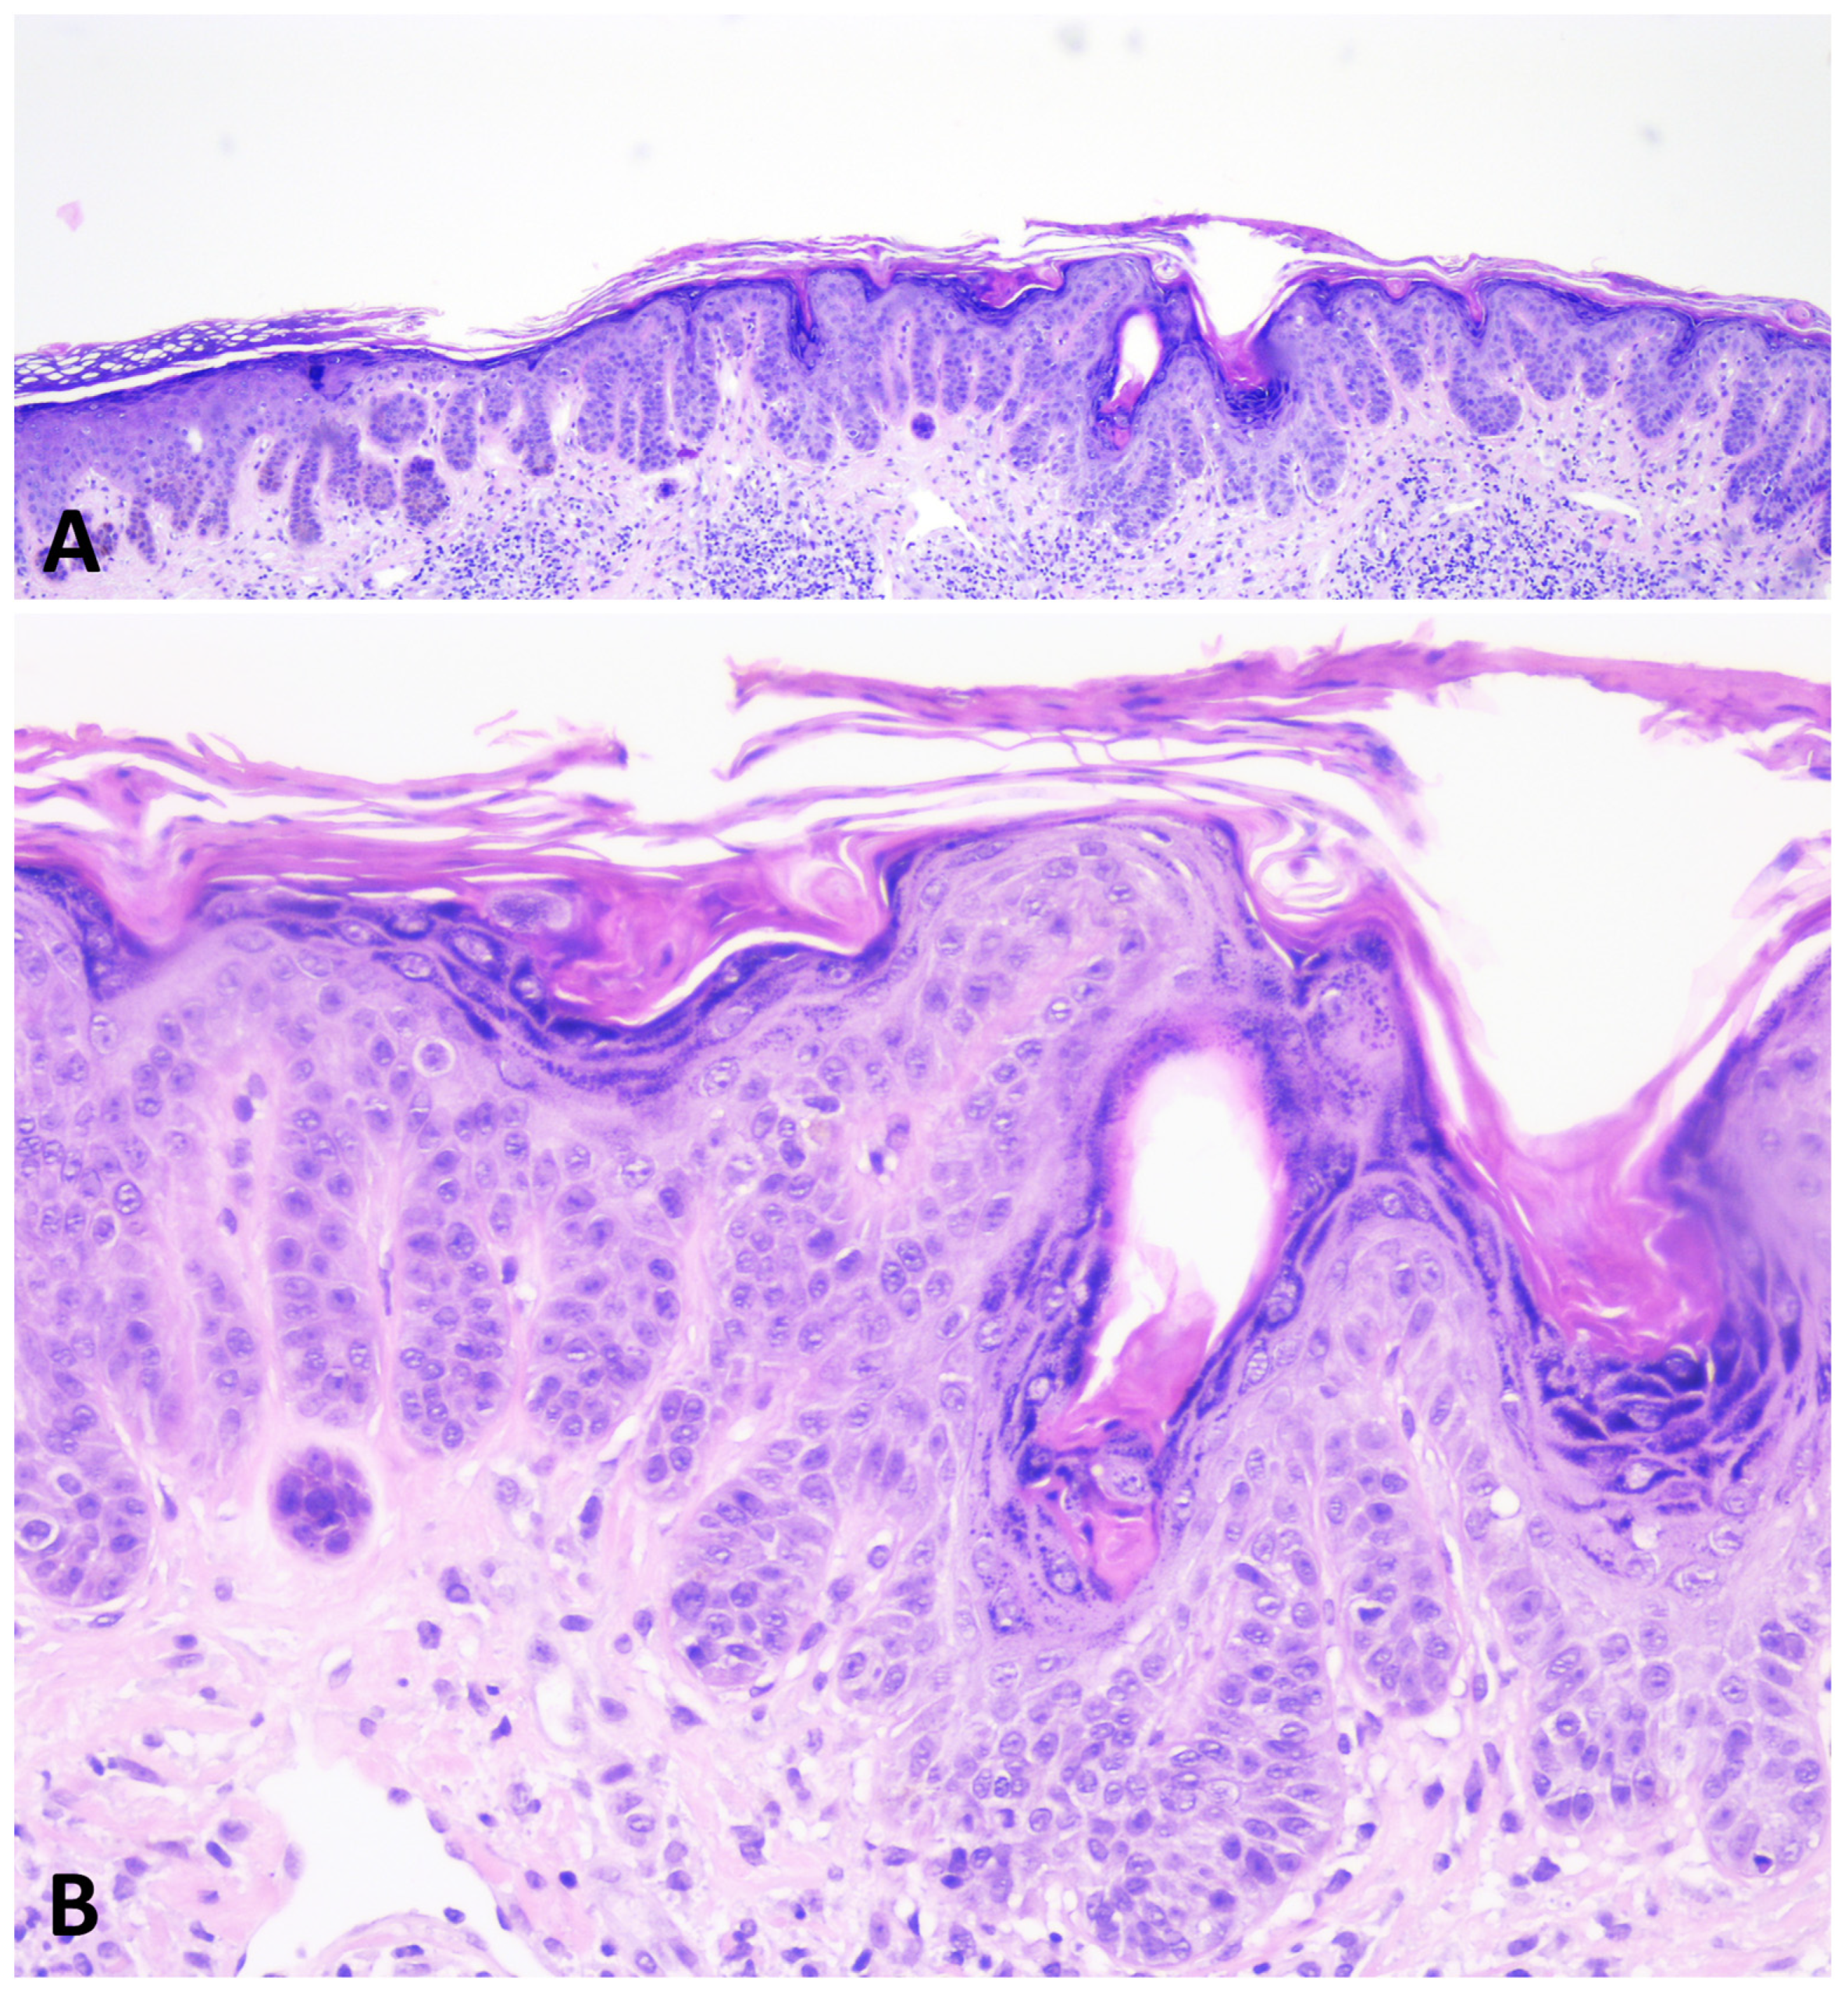

5. Histopathology